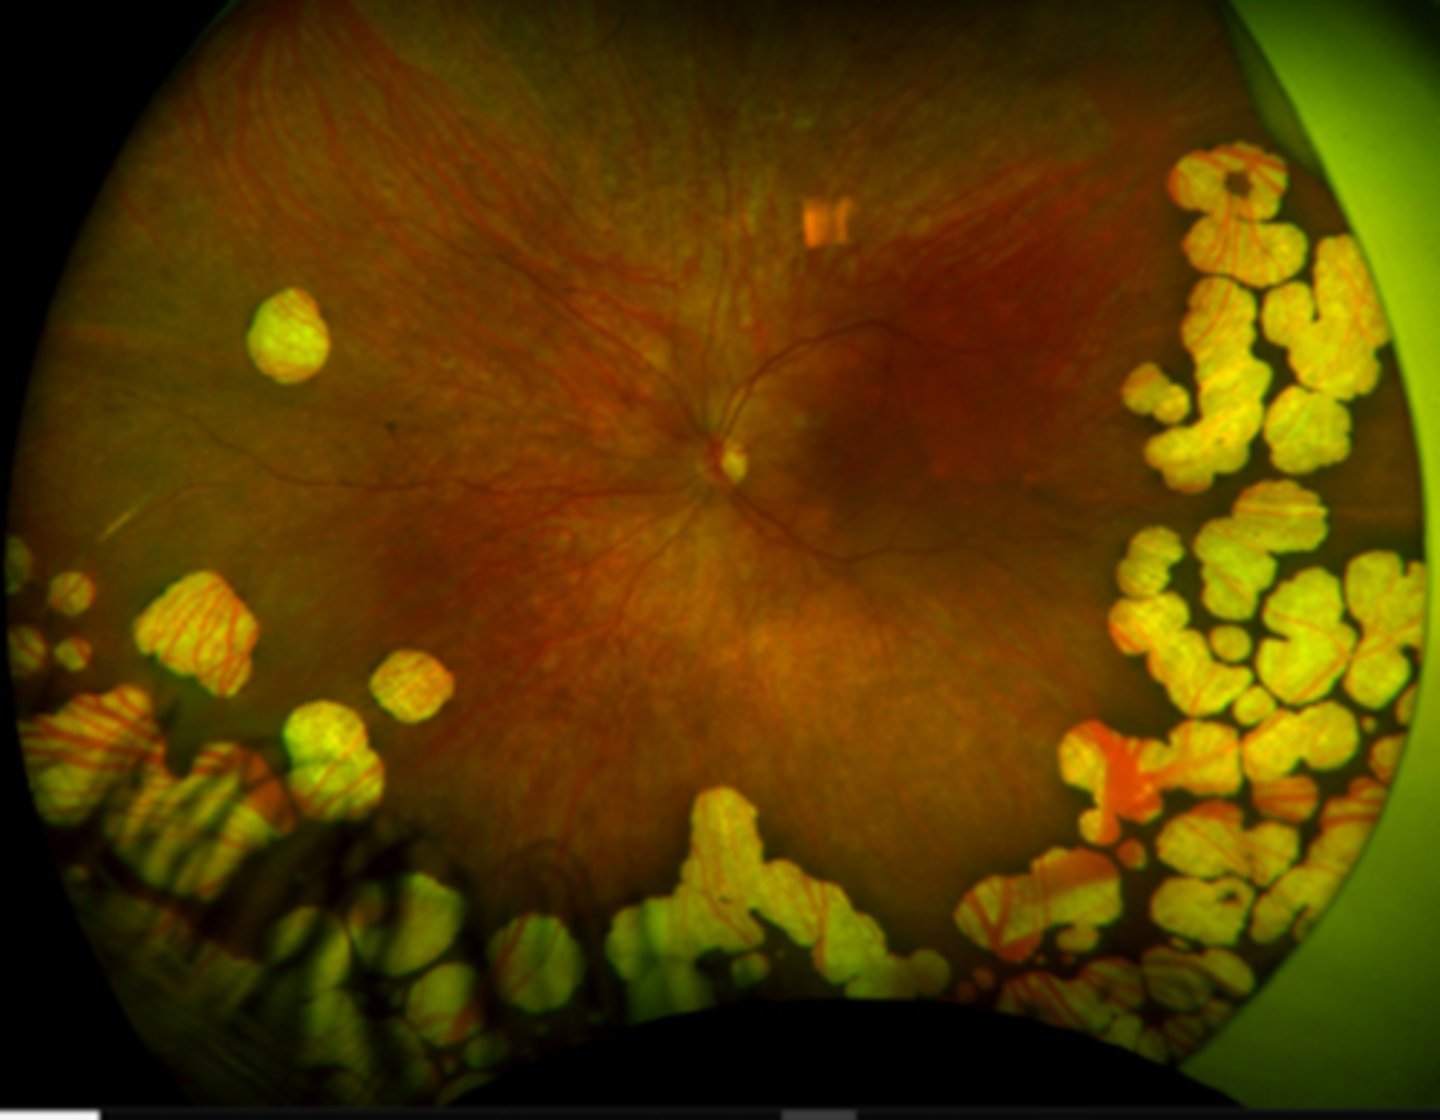

What findings of Leber's Congenital Amaurosis are seen here?

attenuated BV

peripheral pigmentary changes

FAF = peripheral hypopigmented spots and a ring of hyperfluorescence surrounding the fovea